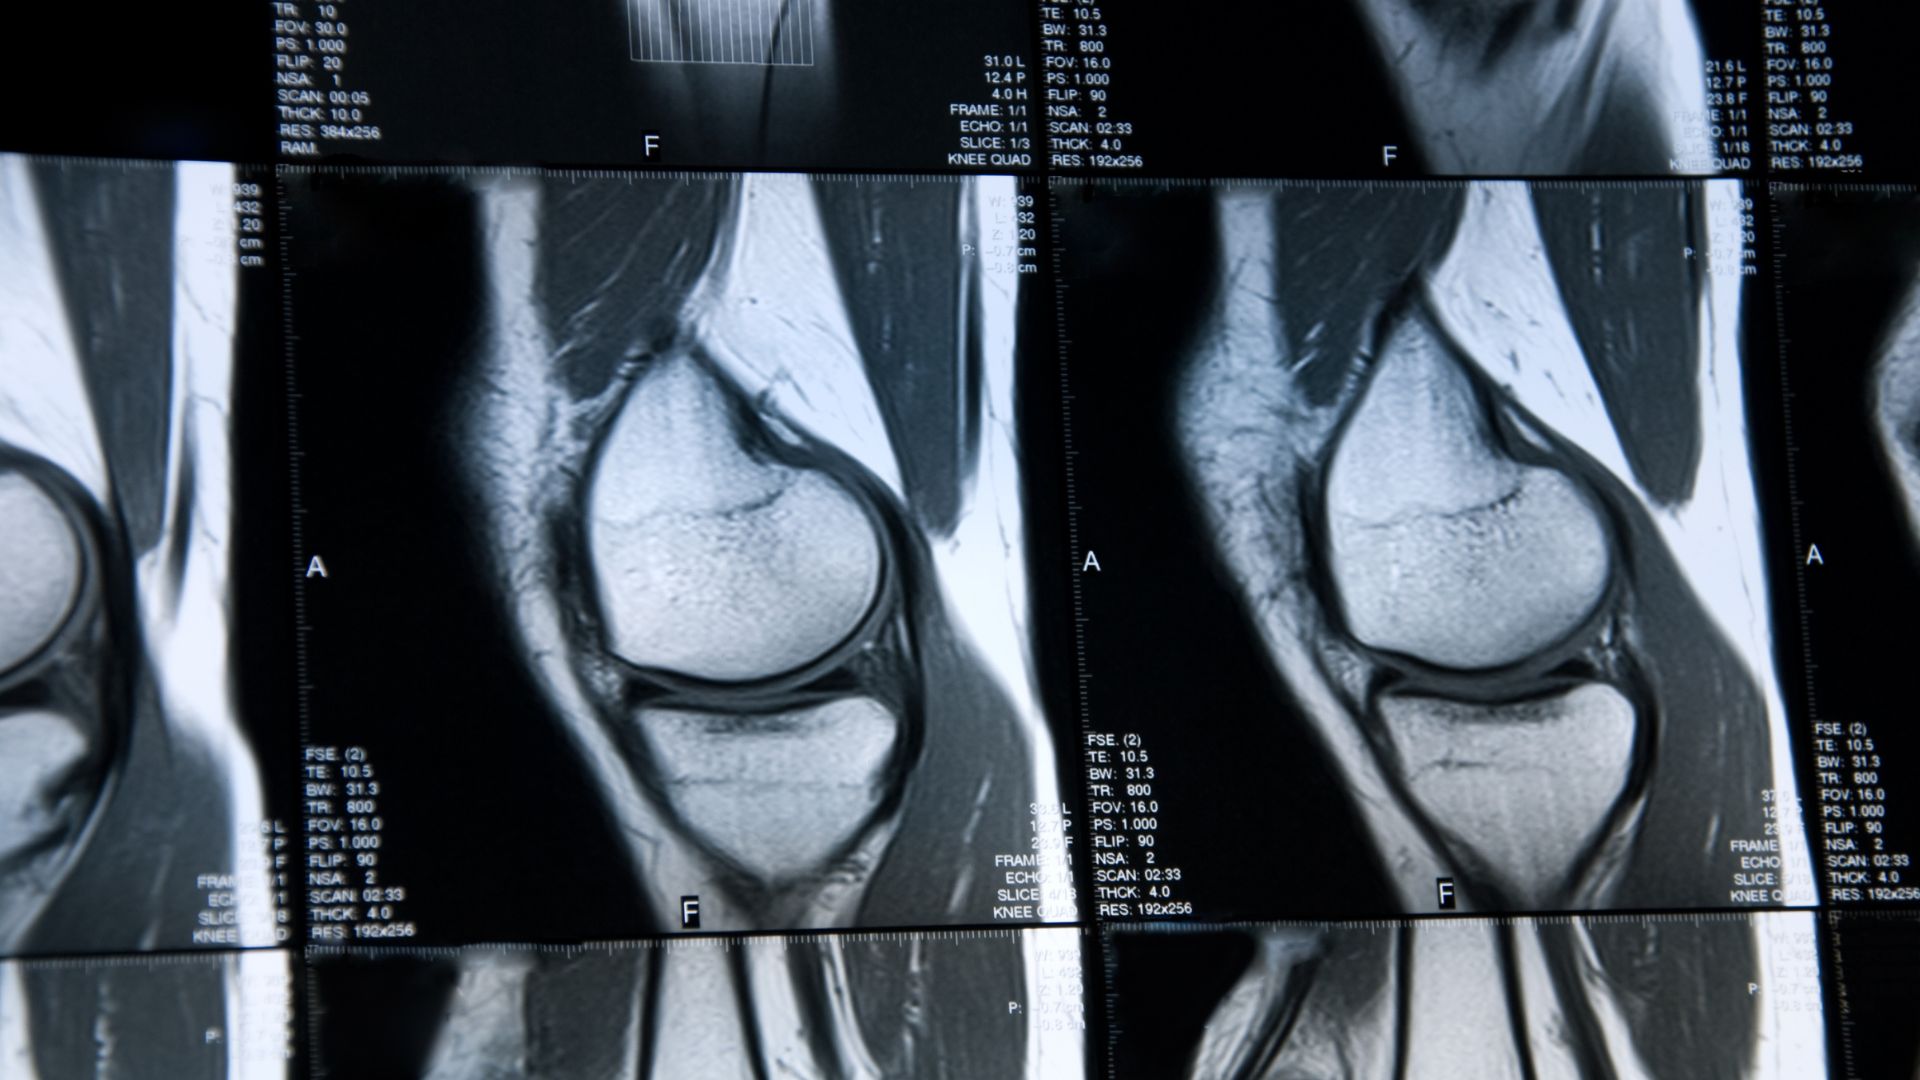

Think of an MRI scan as your knee’s most thorough detective. While X-rays excel at revealing bone issues, MRI technology goes far deeper, capturing an exceptional level of detail of your knee’s soft tissues. These are things like the cartilage cushioning your joints, the ligaments holding everything together, the tendons connecting muscle to bone, and the intricate network of muscles that power your movement.

Unlike other imaging methods, MRI scans use powerful magnetic fields and radio waves to create comprehensive pictures of your joint’s internal structures. This technology proves particularly valuable for knee assessments because the joint contains multiple complex components that work together during movement.